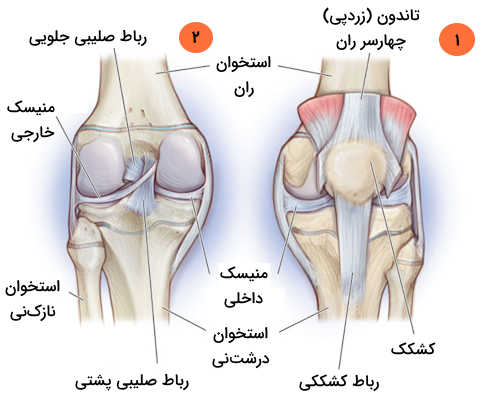

در انتهای استخوان ران دو سطح مفصلی گرد وجود دارند که به آن «کوندیل» (Condyle) میگوییم. کوندیلهای استخوان ران در مقابل دو سطح مفصلی روی استخوان درشتنی قرار دارند که به نسبت صاف به نظر میرسد اما در حقیقت اندکی مقعر است. رباطهای صلیبی که یکی از انواع رباطهای مفصل زانو هستند از فاصله بین دو کوندیل میگذرند و به دو برجستگی کوچک متصل میشوند که بین کوندیلهای استخوان ران و استخوان درشت نی قرار دارند.

کشکک زانو در بخش جلویی استخوان ران قرار دارد و به کمک تاندون زانو یا «تاندون کشککی» (Patellar Tendon) که با عنوان رباط کشکی نیز شناخته میشود، به درشتنی متصل میشود. سطح داخلی کشکک زانو گُوِهای شکل است و با غضروف مفصلی پوشیده شده است؛ این سطح در حین خم یا صاف شدن زانو در امتداد شیاری که روی استخوان ران وجود دارد، میلغزد. استخوان کشکک زانو مانع از لغزش جانبی تاندون میشود، همچنین میتواند اثر استخوان ران به عنوان یک اهرم را افزایش دهد که نتیجه آن تقویت انتقال نیرو است.

این رباطها ضمن متصل کردن فمور یا استخوان ران را به تیبیا یا درشتنی ، آن ها را در جای خود نگه میدارند و از جابهجا شدن موقعیت مکانی این استخوانها جلوگیری میکنند، بنابراین میتوان گفت حفظ ثبات مفصل زانو برعهده رباطها است. رباطهای خارجکپسولی در بخش خارجی کپسول مفصل دیده میشوند و شامل رباطهای زیر هستند.

رباطهای داخل کپسولی در بخش داخلی کپسول مفصلی قرار دارند و معروفترین آنها «رباطهای صلیبی» (Cruciate Ligaments) هستند. در ادامه با هر یک از این رباطها در بخشهایی مجزا بیشتر آشنا میشویم.

رباطهای صلیبی

رباطهای صلیبی زانو در حقیقت دو رباطی هستند که به صورت اُریب از یکدیگر عبور میکنند و به همین دلیل به صورت یک صلیب یا حرف «X» انگلیسی، در درون مفصل به نظر میآیند. با وجود آن که تقاطع این دو رباط در درون کپسول مفصلی است، آنها وارد حفره سینوویال نمیشوند و در خارج از آن قرار دارند. هر یک از این دو رباط صلیبی را با نامی به خصوص میشناسیم که در ادامه با آنها آشنا میشویم.

- «رباط صلیبی جلویی» (Anterior Cruciate Ligament | ACL)

- «رباط صلیبی پشتی» (Posterior Cruciate Ligament | PCL)

رباط صلیبی جلویی

رباط صلیبی جلویی از ناحیه بین کوندیلی جلویی استخوان درشت نی، در پشت محل اتصال منیسک داخلی، منشأ میگیرد، سپس به سمت بالا و بیرون پیشروی میکند تا به بخش پشتی سطح داخلی کوندیل خارجی استخوان ران متصل شود.

این رباط در حین گذر از مفصل زانو و رفتن به سمت دیگر، از زیر «رباط عرضی» میگذرد و سپس به شاخ جلویی منیسک خارجی میپیوندد. رباط صلیبی جلویی نقش مهمی در جلوگیری از چرخش و جابهجایی پشتی کوندیل استخوان ران در حین خم کردن زانو دارد؛ علاوه بر این، رباط صلیبی اجازه «کشش بیش از حد» (Hyperextension) مفصل زانو را نیز نمیدهد.

رباط صلیبی پشتی

رباط صلیبی پشتی از ناحیه بین کوندیلی پشتی استخوان درشتنی منشا میگیرد و به سمت جلویی و میانی پیشروی میکند تا به بخش جلویی سطح خارجی کوندیل داخلی استخوان ران متصل شود. در مقام مقایسه باید گفت که رباط صلیبی پشتی نسبت به رباط صلیبی جلویی دو ویژگی دارد.

منیسکهای زانو

در زانو دو منیسک داخلی و خارجی وجود دارد که هر دو آنها به انتهای ناحیه بین کوندیلی استخوان درشت نی متصل هستند. منیسک داخلی اتصالات دیگری نیز دارد که به شرح زیر هستند.

منیسک داخلی زانو

«منیسک داخلی» (Medial Meniscus) صفحهای فیبروغضروفی با ظاهری هلالی (مشابه با حرف C انگلیسی) و نیمدایرهای است که روی سطح صفحه تیبیای داخلی قرار گرفته است. شاخ جلویی منیسک داخلی به ناحیه بین کوندیلی جلویی درشتنی متصل است و به رباط صلیبی جلویی میپیوندد. شاخ پشتی نیز به ناحیه بین کوندیلی پشتی درشتنی، بین اتصالات منیسک خارجی و رباط صلیبی پشتی، متصل است.

منیسک خارجی زانو

«منیسک خارجی» (Lateral Meniscus) صفحهای فیبروغضروفی و به نسبت دایرهای است که سطح صفحه تیبیای خارجی را میپوشاند. شاخ جلویی این منیسک نیز، مشابه با منیسک داخلی، به ناحیه بین کوندیلی جلویی درشتنی متصل است، اما منیسک خارجی به طور کامل به رباط صلیبی جلویی نمیپیوندد و تا حدی با آن ترکیب میشود. ناحیه پشتی منیسک خارجی به ناحیه بین کوندیلی پشتی در بخش جلویی شاخ پشتی منیسک داخلی متصل است.